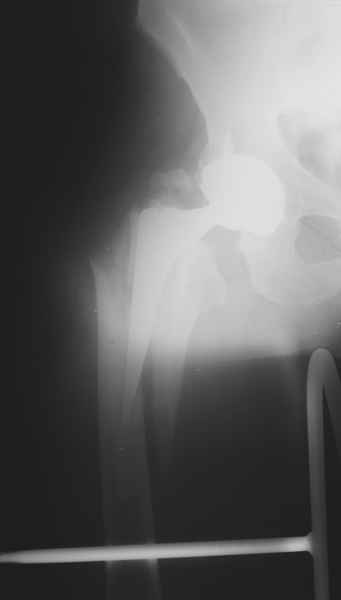

Хочется показать два подобных случая, П-ка Зубарева 72 лет и п-т Гладковский 80 лет. Сразу принимаю замечание, что это были ножки цементной фиксации, просто под руками не было бесцементника.